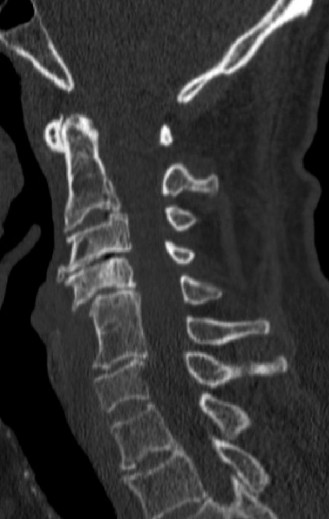

A 63-year-old male sustained a hyperextension injury to his neck while diving into a pool. Upon presentation, he reports decreased sensation in his hands and decreased strength in his arms and wrists, but no lower extremity complaints. On motor examination, he has 5/5 strength in his deltoids and elbow flexors and 4/5 strength in the elbow extensors, wrist extensors, and finger flexors. Lower extremity motor examination is normal. Sensation is decreased to light touch in both hands. Otherwise his sensation is preserved. Images of his cervical spine are shown in Figures 1–1 to 1–3.

Figure 1–1

The correct answer is (B). The clinical scenario describes a patient with central cord syndrome (CCS). CCS continues to be the most common incomplete spinal cord injury accounting for 15.7% to 25% of all spinal cord injuries. The characteristic presentation is an extension moment injury in a previously spondylotic and stenotic spine. Figures 1–1 to 1–3 demonstrate a spondylotic spine with central narrowing and CSF effacement that is worst at the C3–4 level. Bleeding, edema, and/or Wallerian degeneration lead to damage of the lateral corticospinal tract which is the main descending motor tract in the spinal cord. The more central anatomic position of the homunculus to the upper extremities places them at greater risk than those to the lower extremities. As such, injury to the lateral corticospinal tract is characterized by upper more than lower extremity involvement and motor deficits being more pronounced than sensory deficits.